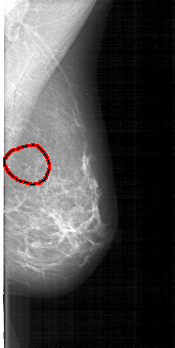

FILE: D_4119_1.LEFT_MLO.OVERLAY

TOTAL_ABNORMALITIES 1

ABNORMALITY 1

LESION_TYPE CALCIFICATION TYPE FINE_LINEAR_BRANCHING DISTRIBUTION LINEAR

ASSESSMENT 3

SUBTLETY 3

PATHOLOGY MALIGNANT

TOTAL_OUTLINES 1

BOUNDARY

LEFT_MLO LINES 5206 PIXELS_PER_LINE 2611 BITS_PER_PIXEL 12 RESOLUTION 43.5 OVERLAY